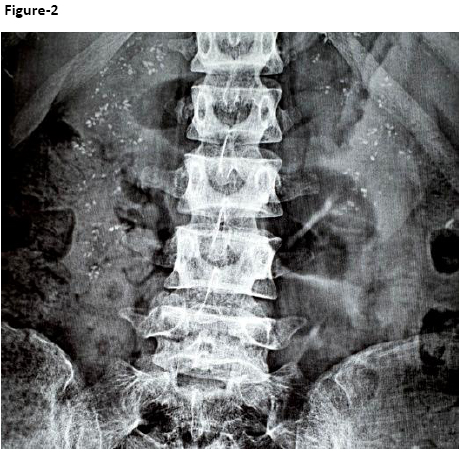

Based on her clinical presentation, she was evaluated to find out the cause of recurrent hypokalemia. Laboratory investigations are shown in Table-1. Investigations revealed hypokalemia, normal anion gap metabolic acidosis and raised urine pH. Urine pH remained high (>5.3) after acid load test. These findings were consistent with distal RTA. She had evidence of microcytic hypochromic anemia with normal iron profile. Hemoglobin (Hb) electrophoresis showed evidence of beta-thalassemia trait. Liver function, renal function and calcium profile were normal. Her autoantibody screen revealed positive anti-nuclear (ANA), anti-Sjogren’s syndrome type A (anti SS-A) and anti-Sjogren’s syndrome type B (anti SS-B) antibodies. All other autoantibodies including anti-double stranded DNA, anti-Scl 70 (topoisomerase I), anti –ribonucleoproteins (anti-RNP), anti-Jo 1, anti-smooth muscle (anti- Sm) were negative. Imaging of the abdomen showed extensive bilateral nephrocalcinosis (Figure-2). Excision biopsy of the supraclavicular lymph node showed reactive lymphadenitis.

Figure-2: Imaging of the abdomen showing extensive bilateral nephrocalcinosis